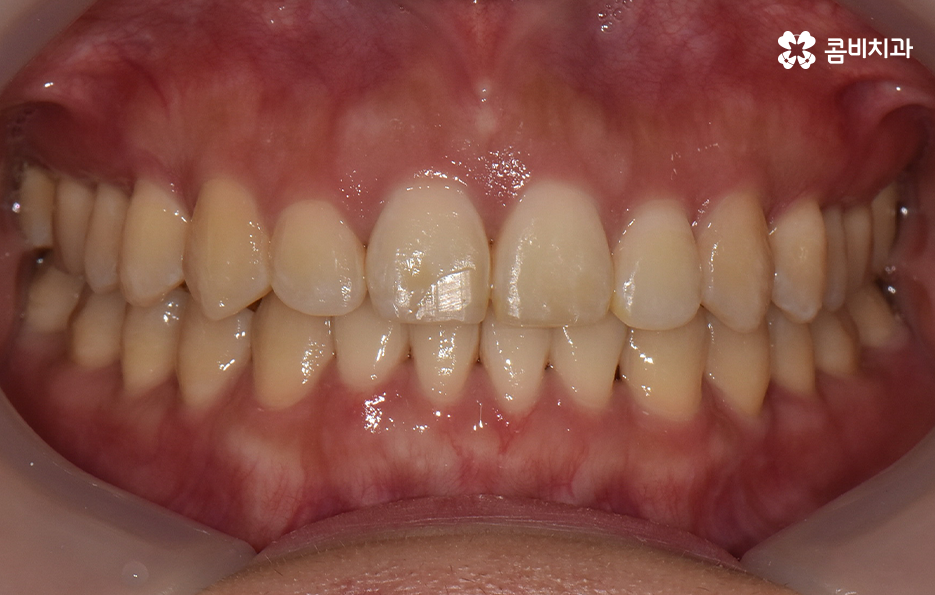

그렇기 때문에 비발치치아교정이 좋다고 생각하기 보다는 개인에 따라서는 치아의 이동 공간 확보를 충분히 하기 위해 발치가 필요한 경우도 있고 얼굴 변화나 부정교합의 개선을 위해 발치가 필수적인 경우도 있을 거예요

반면에 비발치치아교정으로도 충분히 좋은 결과를 얻을 수 있는 경우도 있을텐데 이러한 치료 과정 상의 특징과 장단점을 고려하여 자신의 치료 계획을 경험 많고 숙련된 교정 전문의와 잘 상의하실 필요가 있어요

단순히 비발치치아교정이 발치를 안해도 되니 무조건 좋다고 판단하기 보다는 각 개인의 치료 목적과 구강 및 골격, 얼굴형의 상태를 종합적으로 정밀 검진하여 자신에게 적합한 치료 계획을 잘 세우는 것이 중요하다고 강조드리고 있어요